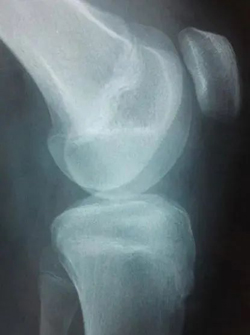

前交叉韧带损伤在儿童和青少年中越来越常见,损伤主要表现为两种形式:韧带实质部损伤和胫骨髁间棘撕脱骨折,团队经过20年的努力,已经将诊断及治疗流程标准化,目前正在科室行政主任杨征带领下承担北京市卫健委迎冬奥国际合作择优资助基金项目:中国儿童青少年前交叉韧带实质部损伤和胫骨髁间棘撕脱骨折诊疗指南的编写工作。

前交叉韧带损伤,箭头为前交叉韧带

胫骨髁间嵴骨折